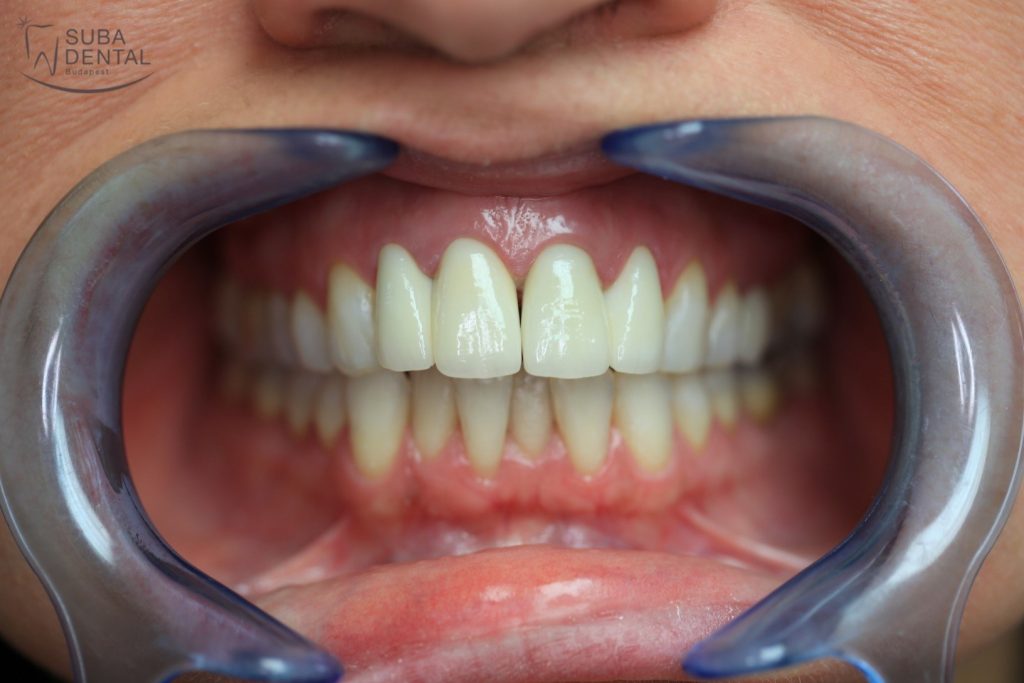

If no adjustments are required following the trial fitting of the matte teeth, the crowns are given their final glossy finish. With the permanent crowns cemented on our patient recovered his self-confidence and feels at ease to smile again.

After